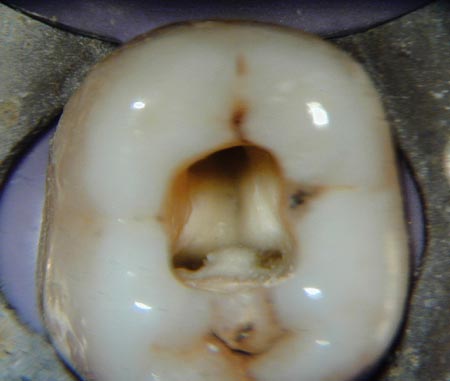

The distal ( rear-most ) root typically just has one canal , but it may have two (which is the case with the tooth shown in this video). That makes for a total of four root canals present in this lower first molar. The procedure involves removing the damaged area of the tooth (the pulp), cleaning and disinfecting it and then filling and sealing it.

A root canal is a treatment to repair and save a badly damaged or infected tooth. The common causes affecting the pulp are a cracked tooth , a deep cavity, repeated dental treatment to the tooth or trauma. After all, a root canal tooth is actually dead tissue. Some professionals feel that it should not be in the mouth at all.

If this infection is allowed to continue to develop without proper treatment, the infection can potentially spread to other teeth in the area or cause illness in other parts of the body. It covers the entire tooth to protect it from further damage. Complete tooth removal – Because teeth are brittle and fracture very easily during extraction,. It is not neede and may have hidden nerve canals which the root canal may not detect or clear out, which could lead to problems after a crown is put on. Root Canal is the area inside the tooth that contains the tooth pulp.